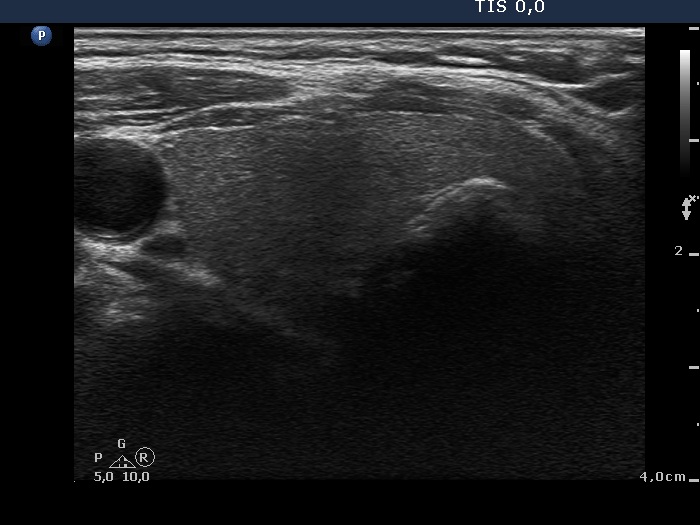

Ultrasonography: the right thyroid was echonormal while the left lobe contained moderately hypoechogenic areas with a 50% echogenicity index. There was a hypoechogenic mass lower and lateral to the right thyroid. The lesion did not present a regular hilum.